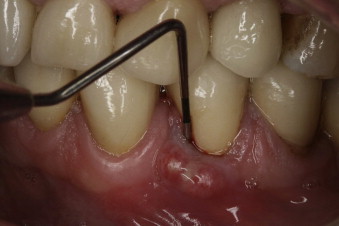

A pocket between the gum and the tooth, near the fracture, where the gum essentially detaches from the tooth

A fistula is a canal that develops between two points to drain an infection from an abscess, and a sinus tract is a drainage canal that originates at a point of infection but has only one ending. Although these terms are used interchangeably in relation to dentistry, a dental fistula is more likely to be a sinus tract infection than an actual fistula. A fistula or tract can take various forms, and the cause and location of the tract helps determine the best treatment method.

The typical indication of a dental fistula or sinus tract is a bump that develops on the gum tissue or gingiva, where it’s called a gum boil, or in proximity to an abscessed tooth. The bump might alternatively appear and disappear, and is a sign that infection exists and your body is using the fistula to drain it. Since draining releases the pressure of the abscess, the fistula itself is often not painful, although many patients report an unpleasant taste.